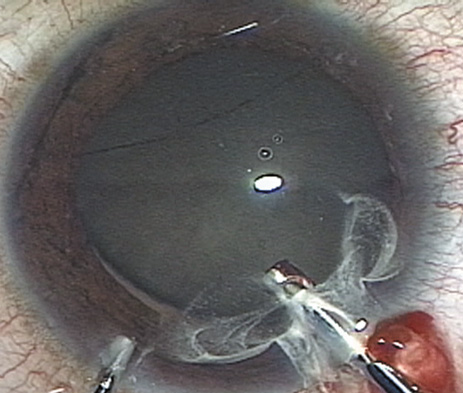

HYDRODISSECTION

Hydrodissection can be performed after the surgeon has successfully completed capsulorrhexis.97 If the capsulorrhexis is not intact, fluid forced around the interior of the capsule may cause the bag to splay open. With capsulorrhexis, hydrodissection is a safe and extremely useful maneuver. Hydrodissection can be thought of as two maneuvers: hydrodelineation and cortical cleaving hydrodissection. By placing a 27-gauge cannula on a syringe filled with balanced saline solution (BSS), the surgeon can direct fluid beneath the residual anterior capsular rim to create a cleavage plane. Depending on the direction the fluid wave takes, different lamellae of the cataract will be separated. Hydrodelineation is the term used when the cleavage plane separates the adult nucleus from the fetal nucleus or the adult nucleus from the more peripheral epinucleus. Hydrodelineation often results in the characteristic golden ring sign (Fig. 11). Cortical cleavage occurs when the cortex is separated from the capsular bag (Fig. 12). Finding the cortical cleavage plane may be facilitated by gently lifting the capsular margin away from the cortex with the BSS cannula before injecting. Several small bursts of fluid allow the surgeon to monitor progress of the fluid wave. When dealing with a soft nucleus, the authors strive to perform true cortical cleaving hydrodissection. For a hard nucleus, hydrodelineation allows manipulation of less of the nuclear bulk, although the remaining epinuclear shell must be addressed in an additional step. Hydrodelineation is particularly useful if the nucleus is not freely mobile after cortical cleaving hydrodissection.

Fig. 11. A crisp “golden ring” is seen from the fluid cleft between the epinucleus and nucleus with hydrodelineation.

Fig. 12. Hydrodissection, performed subincisionally with a 27-gauge J-cannula, produces a cleavage plane between the capsule and the cortex. The small blue arrows indicate the advancing fluid wave.